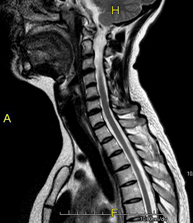

- Cervical spine MRI

This non-invasive diagnostic procedure uses an electromagnetic field and radio waves (from a transmitter and receiver) to acquire high-definition anatomical images of the cervical spine. It is a radiation-free procedure. Indicated for: trauma, spinal degeneration, hernias.

- Cervical + thoracic spine MRI

This non-invasive diagnostic procedure uses an electromagnetic field and radio waves (from a transmitter and receiver) to acquire high-definition anatomical images of the cervical and thoracic spine. It is a radiation-free procedure. Indicated for: trauma, spinal degeneration, hernias.